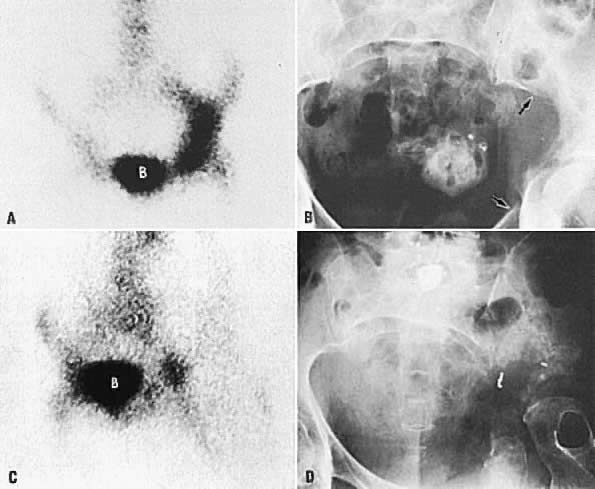

Bone scintigraphy and radiographic skeletal bone survey are the standard imaging procedures for skeletal metastases. Neither imaging modality is indicated in asymptomatic patients. In patients with bone pain, bone scintigraphy should be obtained first in order to identify areas of metastases. Bone radiography is obtained for correlation with positive bone scans. Currently, bone scintigraphy is more sensitive than skeletal survey for detecting early skeletal metastasis.120 The abnormal bone is usually visualized as areas of increased radiotracer activity (Fig. 47A and Fig. 47B); however, in a few cases, the abnormality is imaged as an area of decreased activity (Fig. 47C and Fig. 47D).121 The radiotracer uptake depends on the amount of new osteoid tissue formation. Although CT and MRI are not primary screening techniques for bone metastases, they can detect tumor spread to bone in the pelvis or spine when used for staging of gynecologic malignancies (Fig. 48).

Fig. 47. A. Bone scan shows increased radioisotope uptake in left acetabulum and ilium. B. Radiograph of pelvis shows destruction and some osteoblastic activity in left ilium and acetabular area (between arrows ). C. Bone scan 14 months after A and B shows less activity on the left than is shown in A. Osteoblastic activity at this time is much less than previously shown in A. D. Radiograph demonstrates much larger lytic areas than in B. Acetabulum and adjacent bony areas are completely destroyed. Femur is rotated, but femoral head is intact. ( B, bladder.)